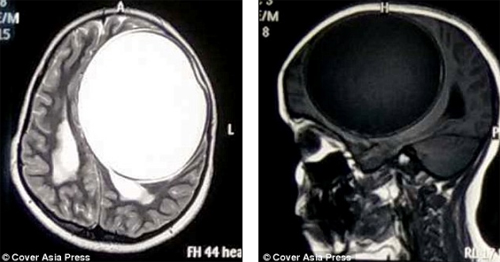

Một cô bé 12 tuổi ở Ấn Độ vừa được phẫu thuật bóc tách nang sán khổng lồ chiếm tới 1/2 kích thước bộ não. Đây được cho là nang sán dây lớn nhất lịch sử y học.

Hai tháng trước, ông Kishor đưa con đến gặp bác sỹ Chirag Solanki, một chuyên gia thần kinh và là bác sỹ phẫu thuật cột sống, tại bệnh viện Sterling ở Gujarat. Sau nhiều lần kiểm tra và chụp MRI, bác sĩ phát hiện khối u nang sán trên não cô bé nặng 675 gram, với kích thước 12,2x11x9,8 cm.

"Khối nang càng lớn khiến cho những cơn đau đầu trở nên tồi tệ hơn. Nang sán này có kích thước bằng 1/2 kích thước bộ não, trông như 1 quả bóng căng phồng và có thể vỡ bất cứ lúc nào", bác sỹ Chirag cho hay.